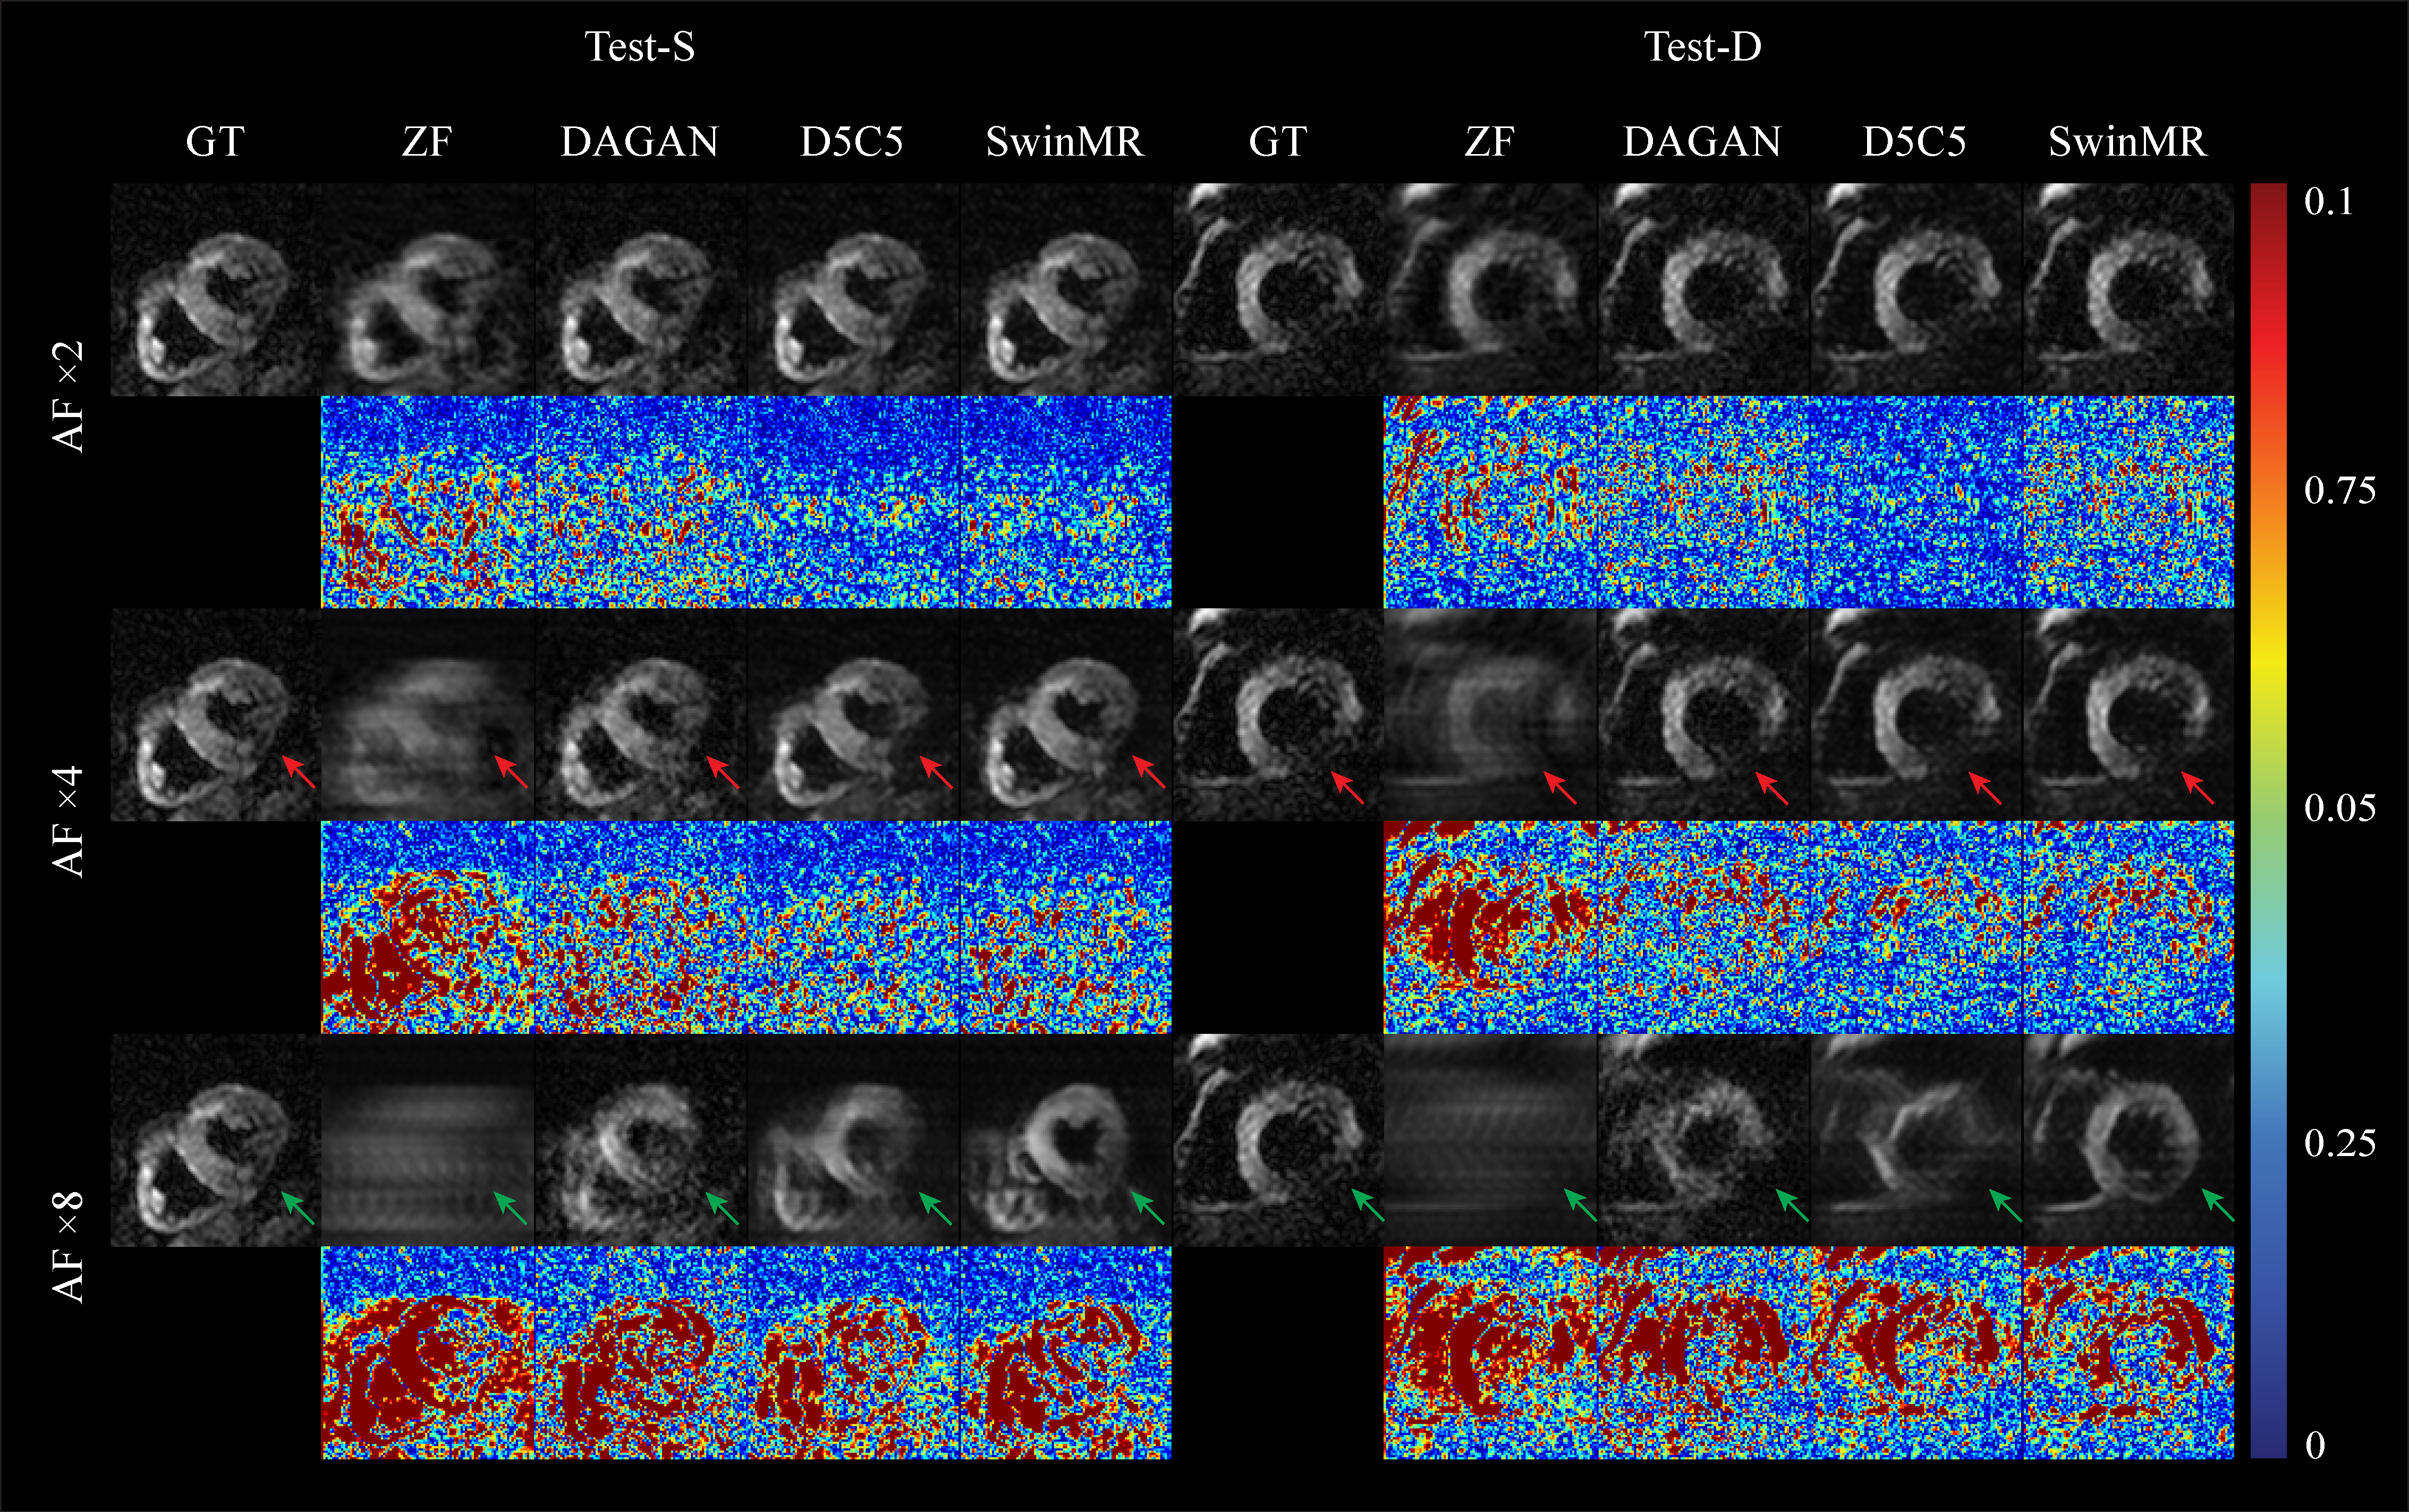

In the context of recovering the high-uncertainty region (green arrow in Figure.2), D5C5 successfully reconstructed the myocardium despite severe aliasing artefacts. DAGAN generated a reconstruction with low SNR and attempted to "in-paint" the missing myocardium based on its prior knowledge influenced by the adversarial learning process. SwinMR preserved most of the myocardium information, but the reconstruction was heavily affected by "fake" details (hallucination).

Figure.2 The visualised samples of the reconstruction on Test-S (systole) and Test-D (diastole) with the undersampling masks of AF ×2, ×4 and ×8.